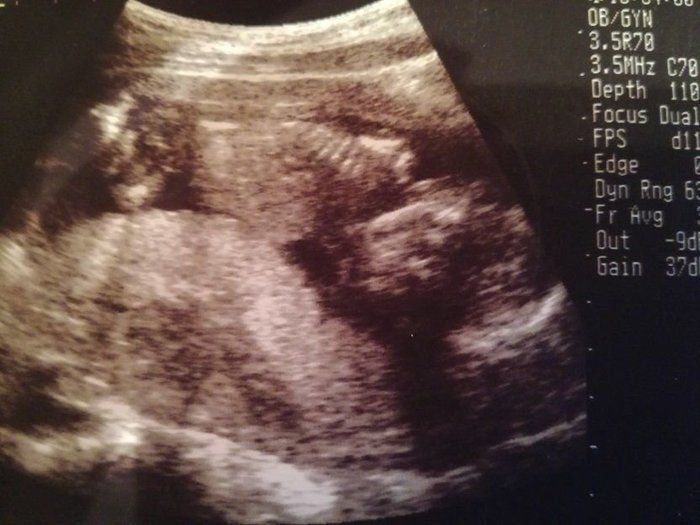

ベビオママさんの妊娠16週目のエコー写真 初めておなかでエコー

赤ちゃんが横向きに写っています。頭は右側で左側がお尻です。赤ちゃんの心臓の動きが、ものすごく早くて驚きました。大人の2倍くらい速い動きだと聞きました。初めて胃と膀胱が確認できました。骨も太くなり、順調に成長していてほっとしました。次の日に初めて胎動を感じました。赤ちゃんが動くと、グニャ、ポコ、グリというような動きが感じられてビックリ! 自分のおなかも大きくなってきて、おへそが横長になってしまいました。